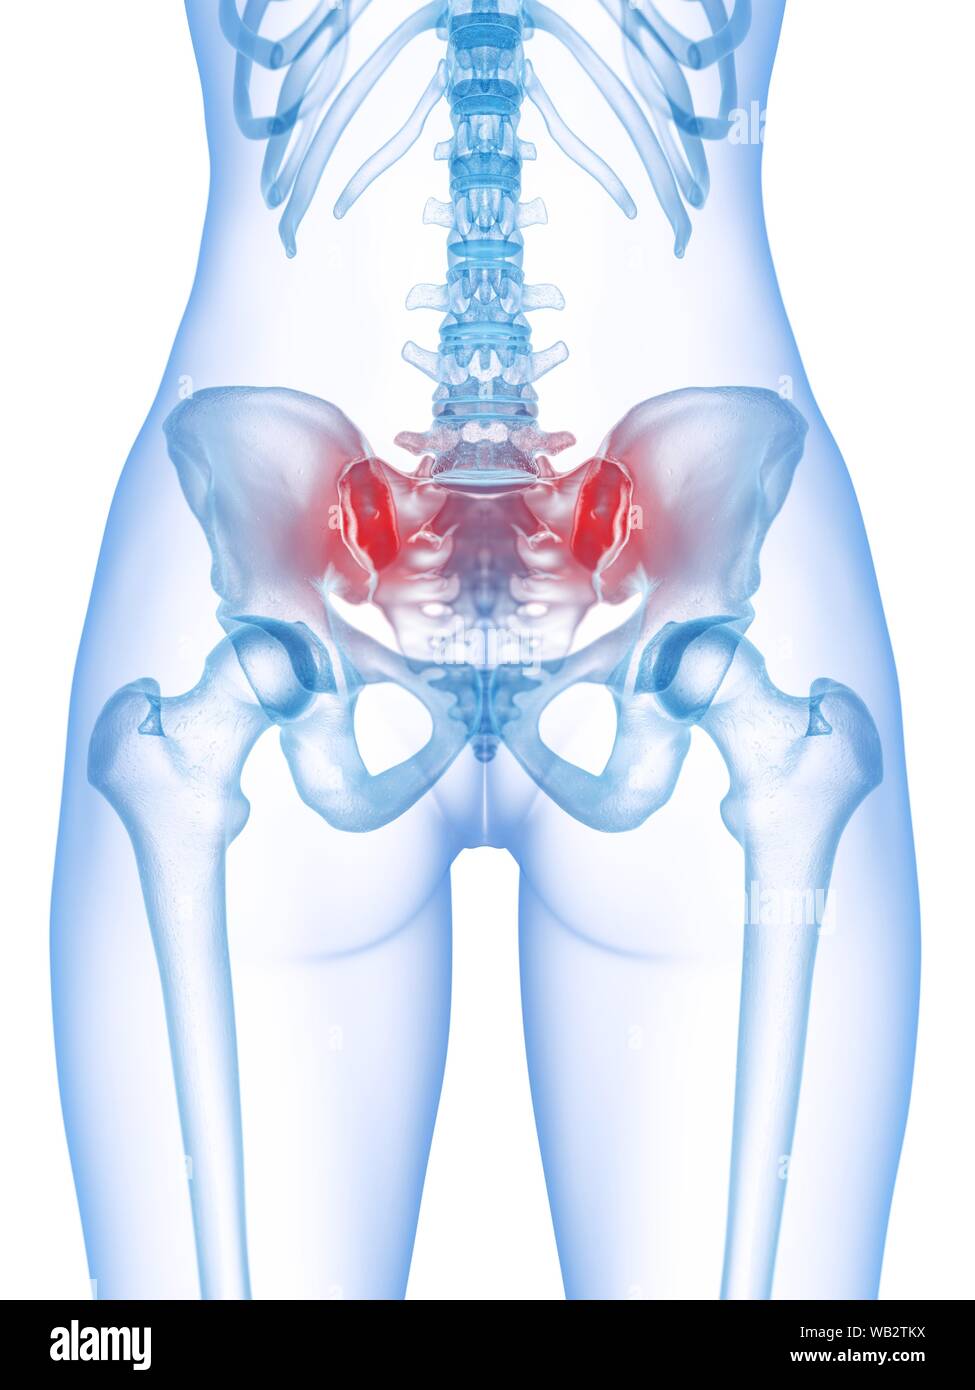

Боль в малом тазу у женщин: Причины и подходы к лечению